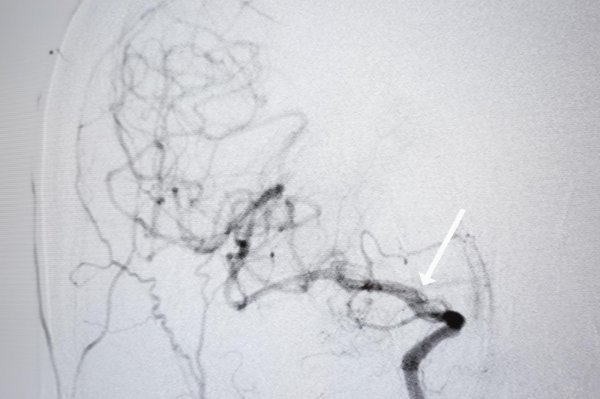

Zahvati kojim se unutar tih šest sati opasni trombovi uklanjaju iz moždane krvne žile već se pet godina veoma uspješno obavljaju u zagrebačkim kliničkim bolničkim centrima Rebro i Sestre milosrdnice, a s vremenom su im se pridružile i kolege iz KBC Split. Na čelu splitske ekipe, koja se ovih dana približava okrugloj brojci od 100 odrađenih zahvata, nalazi se intervencijski neuroradiolog dr. Dragan Dragičević.

Sam zahvat odvija se otprilike na sljedeći način: nakon što pacijent prođe hitni prijam, neurologa te hitni CT i angiografiju koja pokazuje u kojem dijelu mozga je tromb, bolesniku se kroz arteriju u preponi uvodi dugački kateter, sve do mjesta u mozgu gdje se smjestio tromb. Kroz njega potom prolazi manji mikrokateter kojom se provodi takozvani stent retriever. Kad se oslobodi, on se u sljedećih nekoliko minuta raširi u mrežicu kojom se lovi krvni ugrušak.

Krvna žila potom se zatvori balonom kako krv ne bi otplavila tromb, a stent se povlači u kateter, zajedno s trombom. Postupak se ponavlja sve dok se i posljednji komadić tromba ne izvadi iz krvne žile. Druga metoda uključuje nadovezivanje katetera za aspiraciju. Ona se spaja na crpku koja usisava tromb. Izbor metode ovisi o veličini krvnog ugruška i mjestu na kojem se nalazi.

Splitski liječnici brzo su uhvatili dobar ritam. Tehnička uspješnost zahvata na KBC Split iznosi 65 posto, a klinička je još bolja - 76 posto. Tehnička uspješnost govori o otčepljivanju arterije, a klinička pokazuje u kakvom je stanju pacijent nakon operacije, ali i nakon tri mjeseca fizikalnih terapija. A to nije jedno područje u kojem dr. Dragičević vidi veliku priliku za napredak.